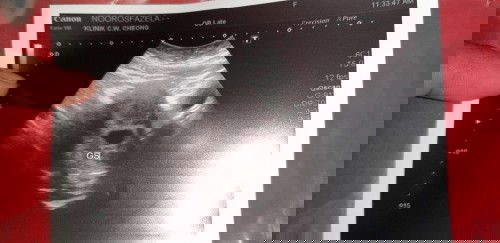

Alhamdulilah penantian 15tahun...first baby harap2 kekal..mummy2 doakan sy ya kuat.. 5week++